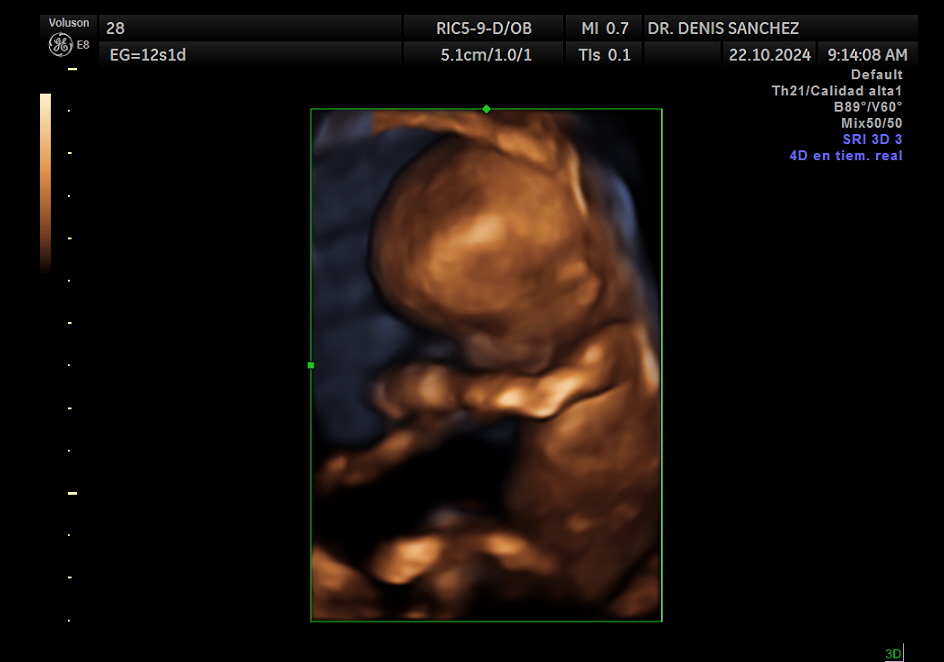

En el consultorio del Dr. Denis Sánchez, en Quito, este examen se realiza con equipos de ecografía de alta resolución, que permiten obtener imágenes precisas y mediciones exactas de estructuras clave del bebé, como la translucencia nucal, el hueso nasal y el flujo sanguíneo fetal mediante Doppler.

Fotografías en color del bebé.